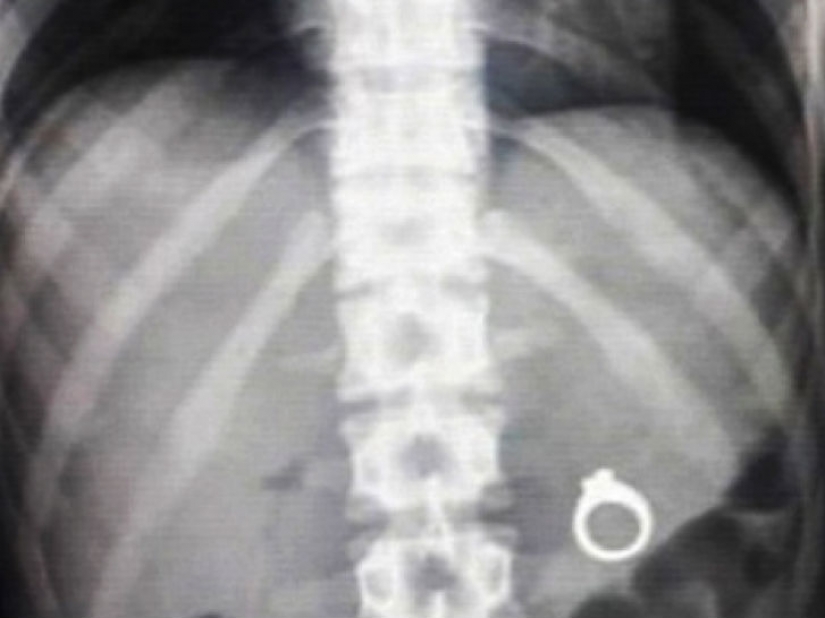

Many men want to be romantic and propose to your sweetheart in some unusual way. And many use, for example, go to hide there's a surprise in the form of a ring. So, men, make an offer before your betrothed decide to try this dish with a surprise.